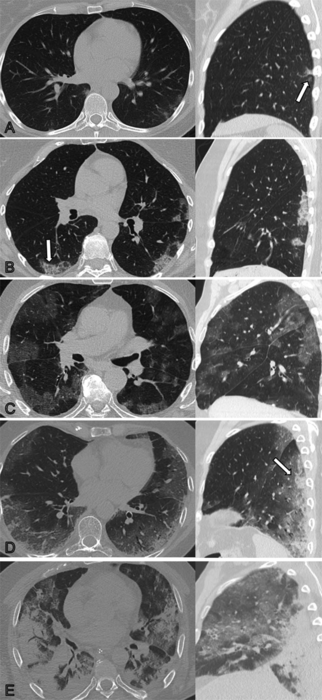

This photo gallery shows the variety of radiological presentations of COVID-19 (SARS-CoV-2) in medical imaging, including computed tomography (CT), radiograph X-rays, ultrasound, echocardiograms and magnetic resonance imaging (MRI). The radiology images show examples of typical COVID pneumonia in the lungs and the numerous complications the virus causes in the body in multiple organs, including the brain, kidneys, heart, abdomen and vascular system.